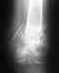

Re: Кость так и не срастается

Да, смысл наложения гипсовой повязки довольно призрачный. И, скорее всего, добиться сращения можно без обнажения концов отломков.

Надо уточнить особенности ситуации путем осмотра и дополнительных снимков, тогда будет больше оснований для выбора дальнейших действий.